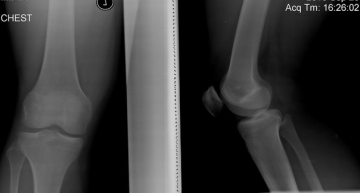

Сейчас мне 32 года . Боли в плечах начались приблизительно в 16 лет после тренировок в тренажерном зале , ещё был момент когда при выполнении упражнения уранил гантели боли стали сильнее. Через некоторое время все вернулось на круги своя , то есть болели но не сильно. Затем перерыв с залом , ушёл служить , в армии было два неправильных падения на спину на локти одно с отягощением в виде бронижелета (18кг) болели сильно затем успокоились , но при отжиманиях ноющая боль возвращалась. Через несколько лет опять спортзал и боли после тренировок проходящие на следующий день, бросил. В повседневной жизни при нагрузках побаливали. Два года назад опять спортзал веса небольшие после перерыва, через недели две боли ушли даже при выполнения физически тяжёлой роботы приблизительно на три месяца. С ростом нагрузки начали опять болеть плечи. Выполняя упражнение жим лёжа не удержал штангу страхующий не успел среагировать, в итоге через несколько дней уже не мог опираться и лежать ни на одной руке сон на животе в определённой позе продолжительность 1,5-2 часа затем бодрствования минут 20. И только после двух недель поход к врачу . Был зделан рентген плечей, зданы анализы , диагноз артроз . Снимка не имею. В детстве часто болел ангиной . Беспокоит в основном левое плечо.

Не видя рентгенограмм проверить диагноз - не реально.

Артроз плечевого сустава (омартроз) в 32 года - это скорее исключение из правил, чем частая патология.

Резюме: очная консультация у травматолога с актуальными рентгенограммами.